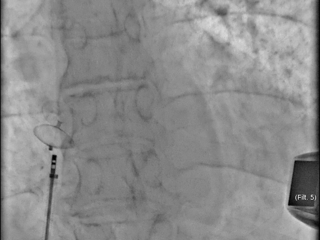

Как проводится хирургическое лечение открытого овального окна? Транскатетерное закрытие аномалии межпредсердной перегородки осуществляется с применением специализированных окклюдерных систем. Процедура проводится под контролем рентгеноскопии и эхокардиографии. Методика включает введение катетера с окклюзионной конструкцией через бедренную вену до достижения правого предсердия. После позиционирования устройства оно раскрывается и надежно фиксируется по обе стороны дефекта в межпредсердной перегородке, обеспечивая эффективное закрытие овального отверстия. В Волынской больнице специалисты первого кардиологического отделения и отделения рентгенохирургических методов диагностики и лечения проводят подготовку и выполняют данный вид хирургического эндоваскулярного вмешательства.